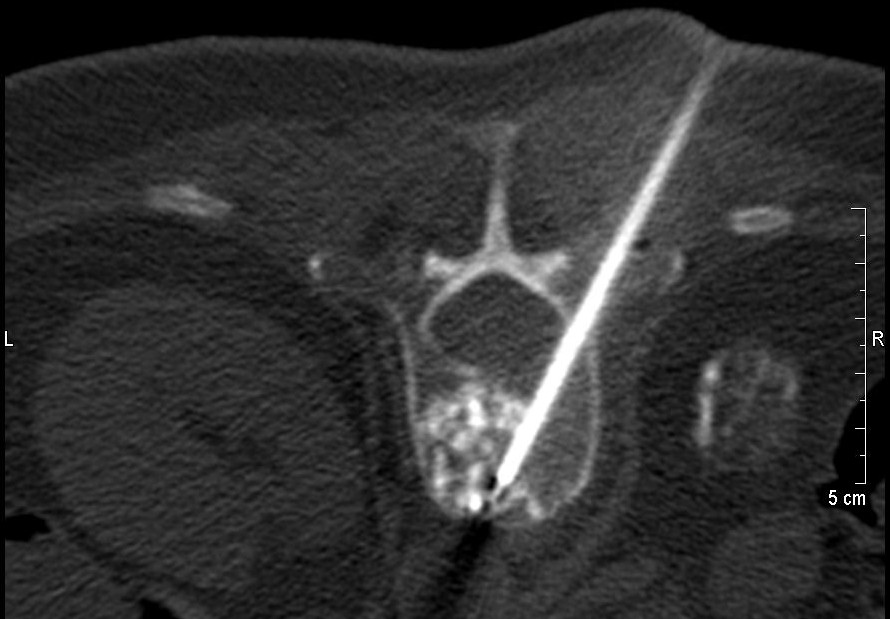

Die Vertebroplastie/Kyphoplastie erfolgt meist in Lokalanästhesie (örtliche Betäubung) mit leichter Sedierung unter modernen bildgebenden Verfahren wie Computertomographie und Röntgendurchleuchtung.

Zur Intervention werden Sie in spezieller Bauchlage auf dem Tomographentisch gelagert und nach üblicher Vorbereitung und steriler Abdeckung des Operationsfeldes, kann mit dem Procedere begonnen werden. Nach Lokalanästhesie der Haut, der Muskulatur und der kleinen Wirbelgelenke, wird die spezielle Vertebroplastiekanüle schonend unter Bildsteuerung in dem gebrochenen Wirbelkörper platziert und nach nochmaliger

Kontrolle wird zuerst eine kleine Menge  Kontrastmittel in den Wirbelkörper injiziert um die später Knochenzementverteilungsmuster zu erkennen. Anschließend bereiten wir der spezielle, für die Vertebroplastie bestimmte Knochenzement vor und injizieren kleine Mengen von ca. 3-5 ml vorsichtig in den porösen gebrochenen Wirbelkörper. Die Zementinjektion erfolgt unter ständiger Bildgebung. Dadurch kann die Verteilung des Zements in dem Wirbelkörper überwacht werden und beim Austritt kann sofort reagiert werden. Der Zement erreicht eine ca. 90% Festigung bereits nach einigen Minuten. Die 100% Festigung wird 24 Std. später erreicht.